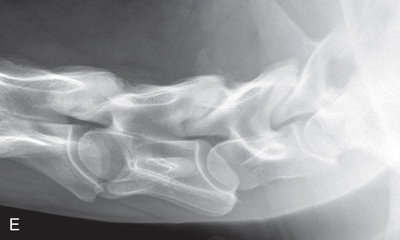

The distal phalanx and the navicular bone comprise the digit or foot. Common indications for imaging the equine foot include localized lameness by clinical examination (pain on pressure from foot testers, increased digital pulses, etc.) or by diagnostic analgesia, laminitis, penetrating wounds, or as required for a prepurchase examination.1

The lateromedial view of the distal phalanx is used for all of the bones and joints of the foot.

Positioning, central ray, and collimation instructions are the same as those for the lateromedial view of the distal phalanx (Fig. 24.14).